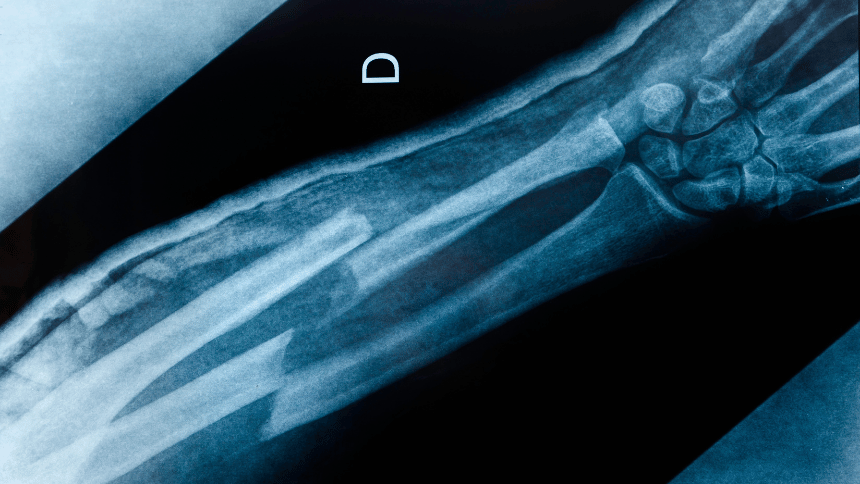

Rozdíl mezi otevřenou a zavřenou zlomeninou

Otevřená zlomenina neboli složená, je vážnější, protože kost při zlomení prorazí kůži. Před zafixováním do sádry se zlomenina často chirurgicky čistí, aby se odstranily nečistoty a snížilo riziko infekce.

Forma lomné linie

Příčné linie jsou rovné a probíhají přes kost, spirální zlomenina se při zlomení zkroutí a zlomenina zelené větvičky popisuje pouze částečné nalomení kosti, typické zejména pro dětské pacienty, kdy se kost ohýbá a praskne jen z jedné strany.

Dle počtu úlomků

Podle počtu úlomků se zlomeniny rozdělují na segmentální, kdy je kost zlomena na dvou nebo více místech, tříštivé, které vytvářejí několik úlomků, a avulzní, kdy se malý kousek kosti odtrhne od hlavní části.